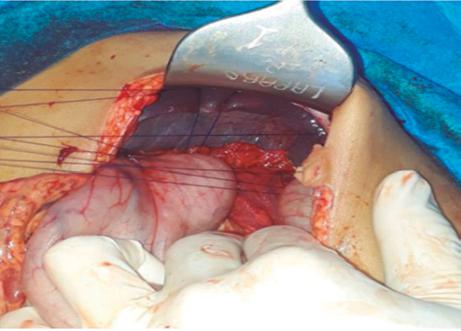

En primer tiempo laparoscópico, se evidenció división del ligamento gastroesplénico por el antecedente quirúrgico descrito, bazo ectópico en fosa iliaca derecha con proceso inflamatorio perivisceral y el pedículo vascular esplénico rotado en 720° (Ver Figura 3.A). Se realizó detorsión del pedículo vascular y ante la no claridad de la relación del mismo con el meso del colon, se realizó laparotomía exploratoria, logrando recuperación del flujo vascular del bazo, por lo que se realizó conservación esplénica con esplenopexia a nivel de hipocondrio izquierdo, utilizando 4 puntos separados de Prolene vascular 3-0 entre el diafragma y el peritoneo parietal lateral de la pared abdominal, y rotando un colgajo pediculado de omento mayor para evitar efecto de cizallamiento esplénico con el material de sutura.(Ver Figura 3.C)

Figura 3.A Hallazgo intraoperatorio. Bazo en ubicación ectópica en fosa ilíaca derecha, con pedículo laxo, torsión del mismo y con signos de isquemia.

Figura 3.B Hallazgo intraoperatorio. Bazo posterior a la detorsión del pedículo vascular, con mejoría de la perfusión del órgano.

Figura 3.C Esplenopexia con suturas de prolene vascular 3-0, entre peritoneo parietal y diafragma.